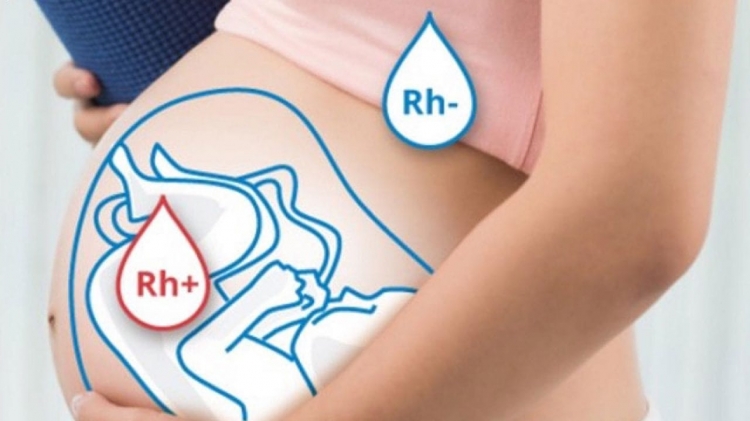

Ebevynler tarafından '' kan uyuşmazlığı nedir, tedavisi mümkün mü, çocuğu nasıl etkiler?'' sorularının yanıtları merak ediliyor. Gebelik sırasında anne kanına geçen bebeğe ait Rh pozitif kan hücreleri annenin bağışıklık sistemini uyarır ve antikor üretimini başlatır. Bu antikorlar ise bebeğe ait kan hücrelerini parçalar. Bu duruma Rh kan uyuşmazlığı denir.

Rh uyuşmazlığı, bir annenin Rh negatif kanı olduğunda ve bebek Rh pozitif kanı olduğunda ortaya çıkar. Annenin vücudu fetüsün veya yenidoğanın kan hücrelerine bir bakteri veya viral istilacıymış gibi saldıran otomatik bağışıklık tepkisi üretecektir. Bu immün yanıtın gelişmesi oldukça yavaştır ve ilk gebeliklerde nadiren ciddi bir konudur. Bununla birlikte, Rh uyumsuzluğu olan sonraki gebelikler önemli ölçüde daha yüksek bir risktir.